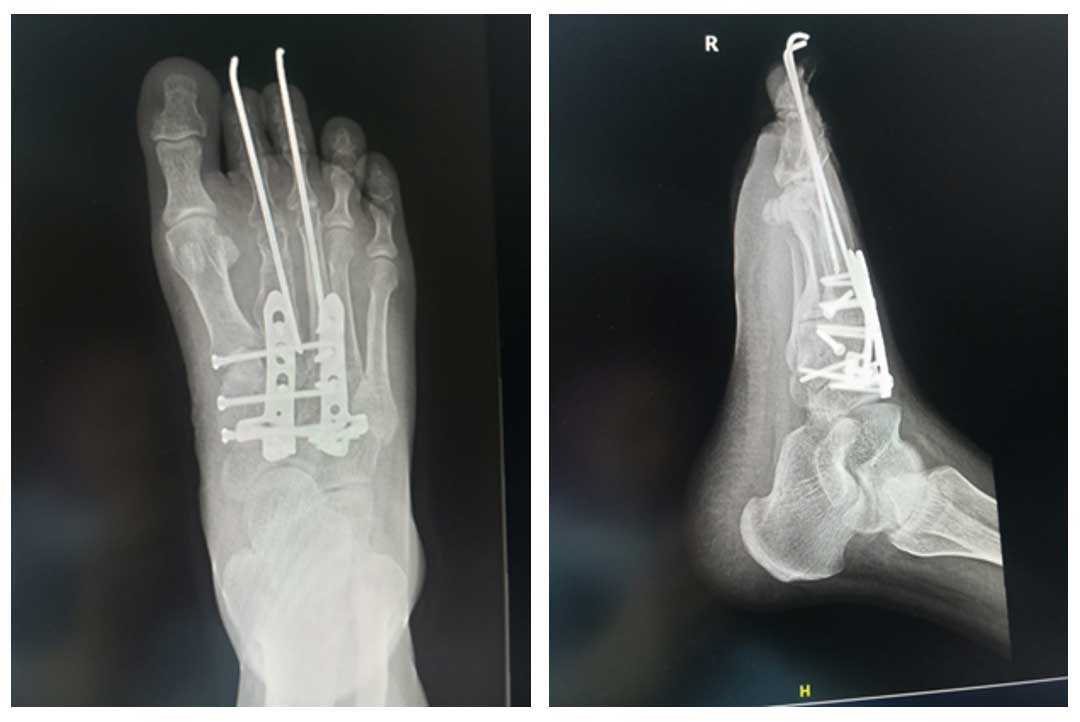

Ameliyat Sonrası: Rezeksiyon sonrası sıvı azot ile geri kazanılan kemiğin plak, vida ve K telleri ile fiksasyonu görülmekte.